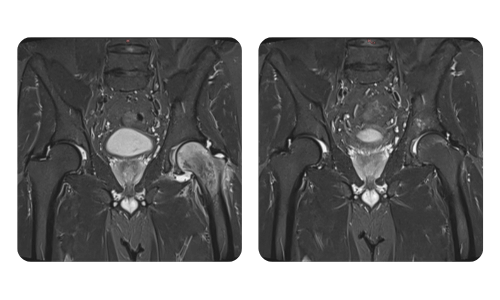

I progressi dei nostri pazienti, misurati prima e dopo la terapia iperbarica, riflettono l'efficacia e l'impatto positivo del trattamento. Scopri i risultati documentati della terapia iperbarica presso la clinica Hyperbarium Oradea, basati su valutazioni cliniche e dati oggettivi che evidenziano miglioramenti significativi in diverse condizioni.